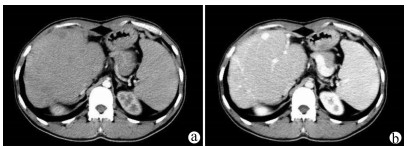

Application of liver three-dimensional visualized reconstruction technique in hepatectomy for children with complicated hepatoblastoma

Di ZHAO, Jindong YE, Huali LI, Kui JIN, Xiang LIU, Xiaoran LI, Liuxin DUAN, Jungui LIU, Wei LYU, Weihong DUAN, Quanda LIU

2021, 37(9): 2130-2135. DOI: 10.3969/j.issn.1001-5256.2021.09.025

Abstract(1328) HTML (405) PDF (3973KB)(66)

Abstract:

Objective  To investigate the application of liver three-dimensional (3D) visualized reconstruction technique in hepatectomy for children with complicated hepatoblastoma.  Methods  A retrospective analysis was performed for the clinical data of 30 children with hepatoblastoma who underwent hepatectomy for radical resection in PLA Rocket Force Characteristic Medical Center from January 2018 to October 2020, and according to whether liver 3D visualization with IQQA-Liver system was performed before surgery, the children were divided into 3D reconstruction group with 15 children and control group with 15 children. The two groups were compared in terms of perioperative parameters, short-term prognosis, and follow-up conditions. The independent samples t-test was used for comparison of normally distributed continuous data between two groups, and the Mann-Whitney U test was used for comparison of non-normally distributed continuous data between two groups; the Fisher's exact test was used for comparison of categorical data between two groups.  Results  Compared with the control group, the 3D reconstruction group had a significantly higher mean age (55.7±10.2 years vs 28.2±2.7 years, P < 0.05) and a significantly higher number of patients with POSTTEXT stage III/VI hepatoblastoma (12 vs 5, P < 0.05) or involvement of the hepatic vein or the inferior vena cava (11 vs 3, P < 0.05). All children completed the surgery successfully, and there were no significant differences between the two groups in blood loss, time of operation, number of times and duration of hepatic portal occlusion, and number of children receiving segmental hepatectomy or partial hepatectomy (all P > 0.05). The median follow-up after surgery was 9.5 months. In the 3D reconstruction group, 2 children experienced recurrence and were diagnosed at 10 and 12 months, respectively, after surgery, and they were treated with chemotherapy at the moment; in the control group, 4 children experienced recurrence, which was higher than that in the 3D reconstruction group (P=0.651), and among these 4 children, 2 had recurrence at 7 months after surgery, received liver transplantation, and survived up to now, and the other 2 children died shortly after recurrence.  Conclusion  3D visualized reconstruction technique helps to perform hepatectomy for children with complicated hepatoblastoma more safely and accurately, especially extended hepatectomy for patients with stage POST TEXT III/IV hepatoblastoma, thereby avoiding liver transplantation.